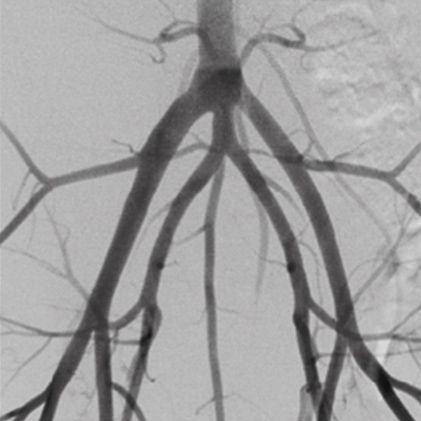

26cm*26cm Flat Panel Detector provides excellent image quality (Max. 6.8MP) with large FOV(*). * Field Of View

DSA(Digital Subtraction Angiography) helps various clinical diagnosis and procedures through the vessel image information after injecting contrast medium.